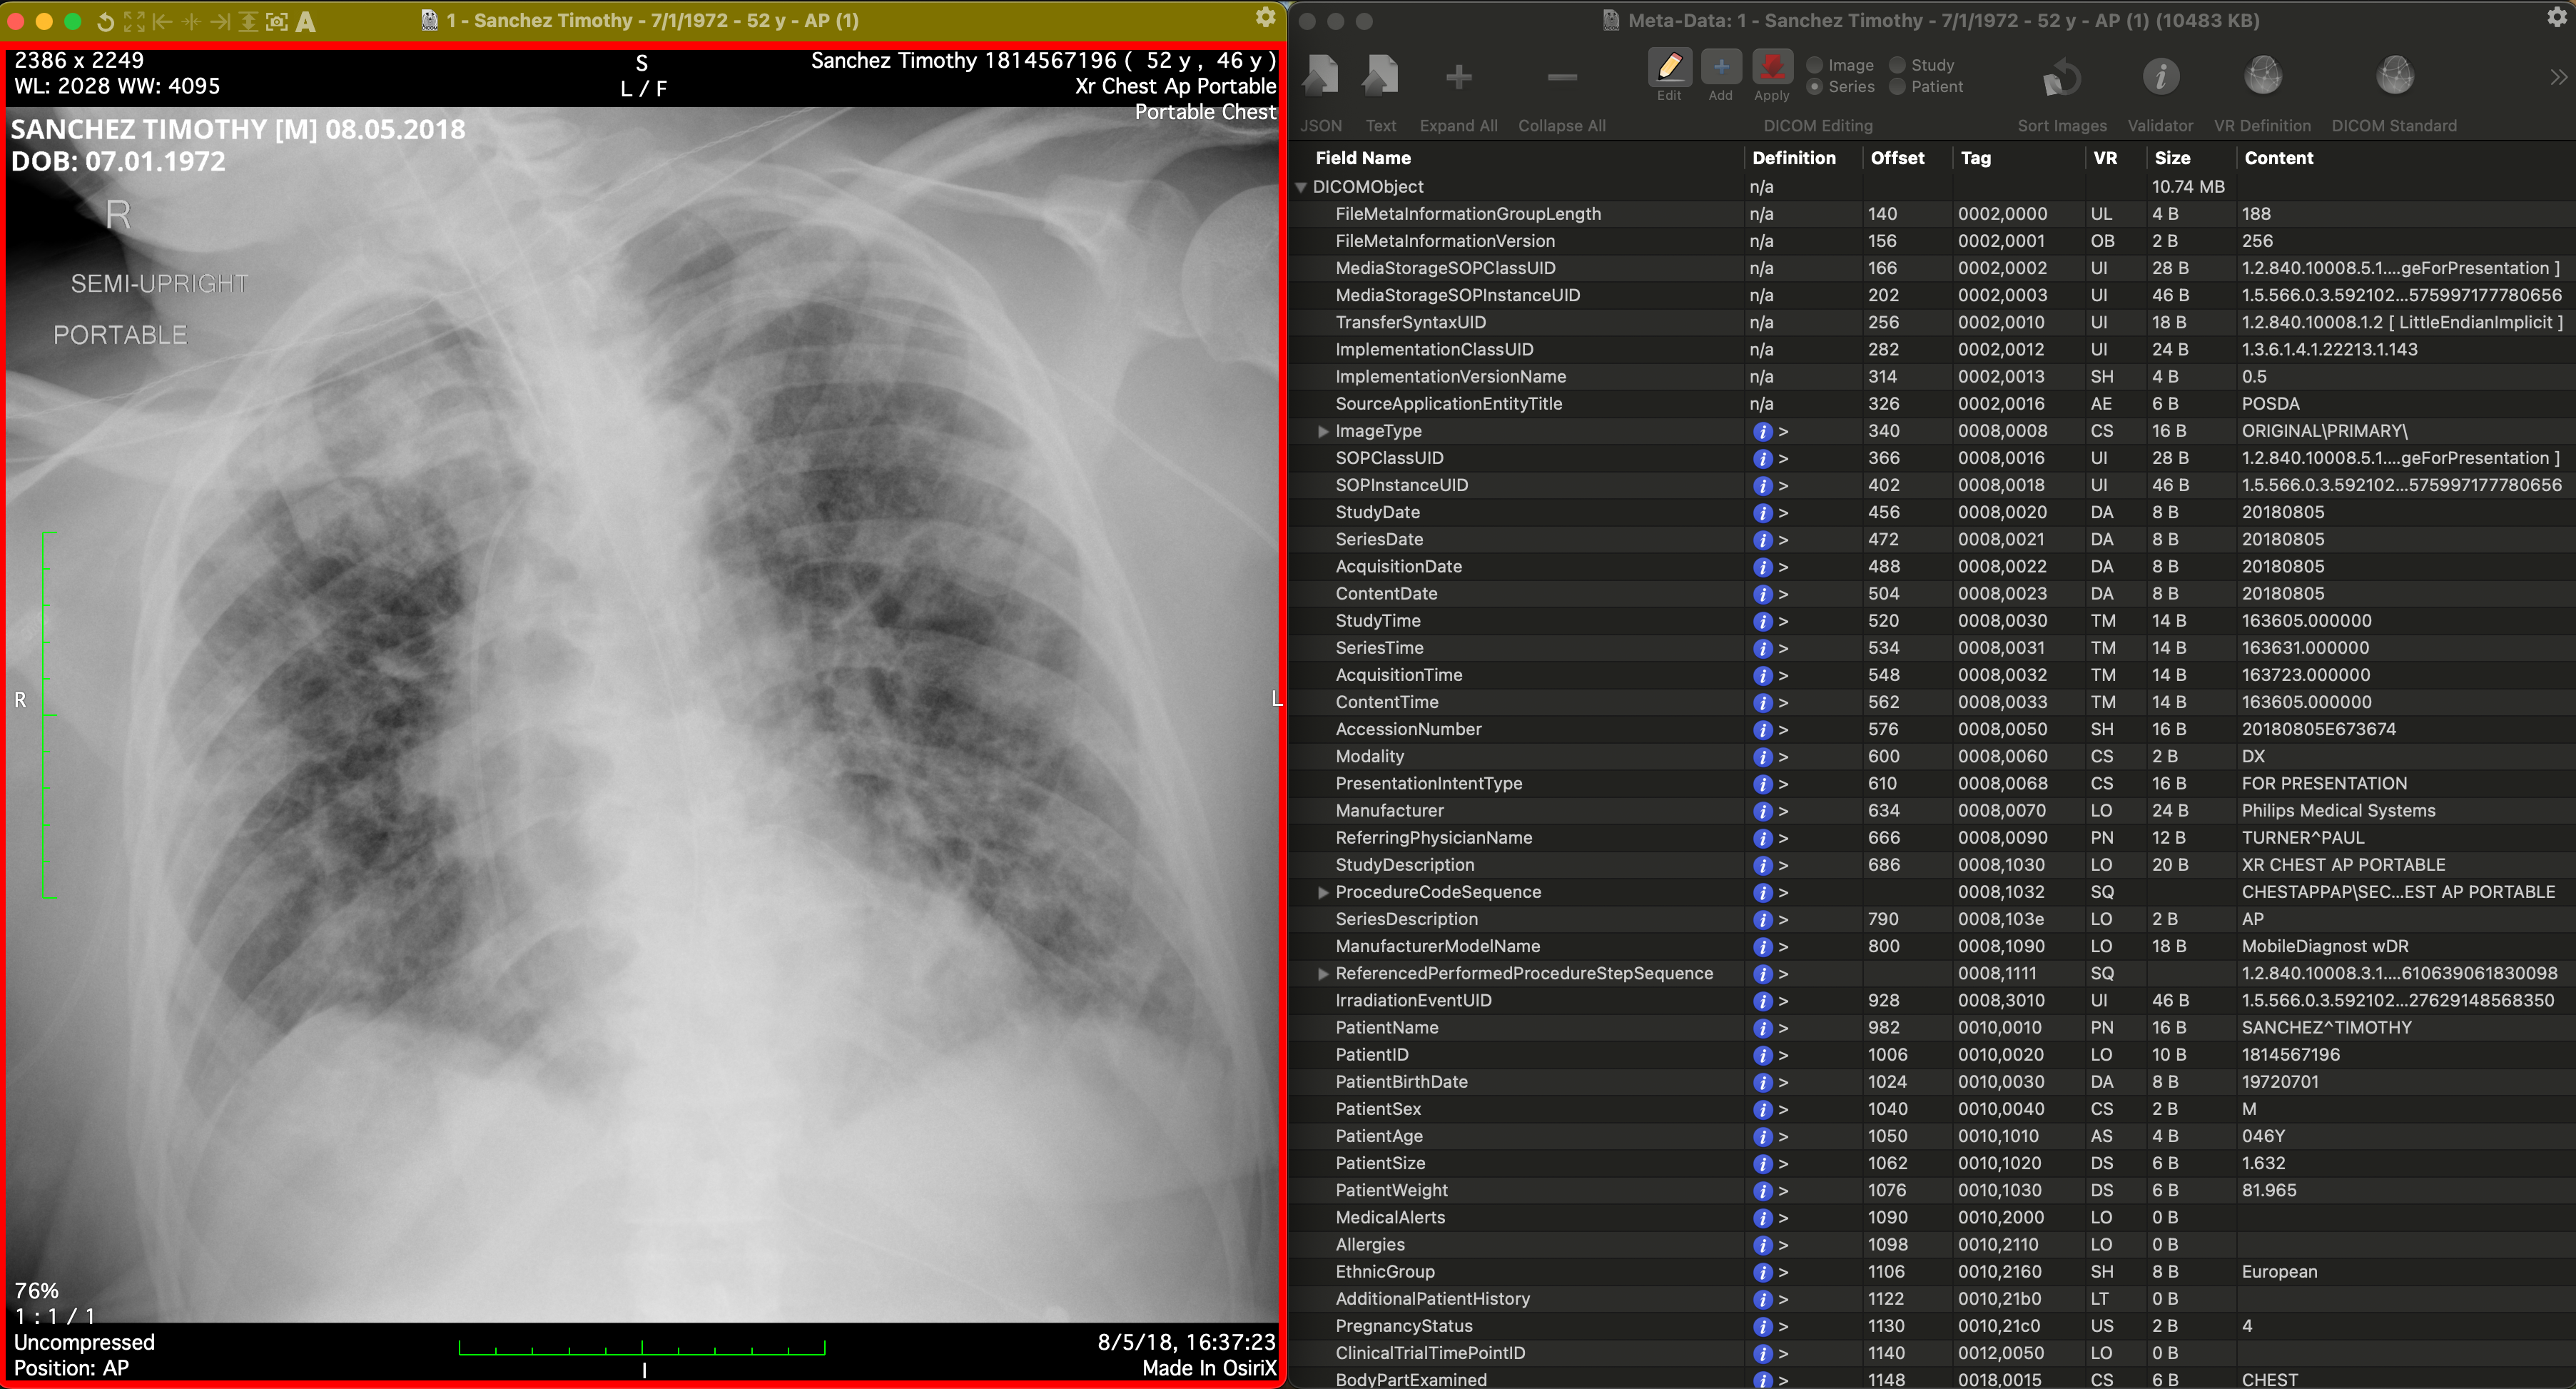

The Digital Imaging and Communications in Medicine (DICOM) standard, which is widely adopted for medical imaging, embeds patient-related information as metadata in the DICOM files. For some modalities, manufacturers embed certain PHI/PII, such as patient name and date of birth, in the pixel matrix of images, such as for ultrasound (Bidgood Jr et al., 1997; Mildenberger et al., 2002). DICOM data elements used as attributes of information objects are identified by numeric tags (group number and element number), with even-numbered group numbers representing standard attributes, and odd-numbered groups representing private attributes specific to manufacturers. In a DICOM medical image, many identifiers are stored as predefined attributes in the DICOM header. These include the Patient’s Name (0010, 0010), and Patient’s Birth Date (0010, 0030), etc. PHI/PII can be present in either such structured DICOM attributes intended for the purpose, but also in free-text fields, such as Additional Patient History (0010, 21B0). Header and pixel data of DICOM images must, therefore, be de-identified. Fiugre 1 shows a DICOM image comparison before and after deID. The well-defined structure of fixed DICOM attributes allows for semi-automatic deID to remove corresponding PHI/PII with relative reliability, but requiring verification, using tools such as The Radiological Society of North America (RSNA) Clinical Trial Processor (CTP) (Freymann et al., 2012), DICOM Library (Macdonald et al., 2024), and XNAT platform (Clunie et al., 2024). Recently, the technologies of medical image deID have evolved from strict rule-based systems to include hybrid approaches such as deep-learning-based systems for object character recognition in pixel images, and large language models (LLMs) for detection of PHI/PII within free text fields (Langlois et al., 2024; Kopchick et al., 2022). The DICOM deID process for removing sensitive information needs to follow instructions of a set of deID standards such as those in DICOM PS3.15 (National Electrical Manufacturers Association (2025), NEMA) for PHI/PII fields to remove or modify, and satisfy HIPAA DeID requirements.

Improper pixel image deID may be partial, such as the retention of partial PHI/PII information or the removal of non-PHI/PII information. In the top-row of Figure 4, the deID process result contains false negatives. For example, only the last name is de-identified in the example, while the first name remains. In the bottom-row of Figure 4, the text ’SEMI-UPRIGHT’ at the position of the bottom red box has been misrecognized as PHI/PII information and then incorrectly redacted.